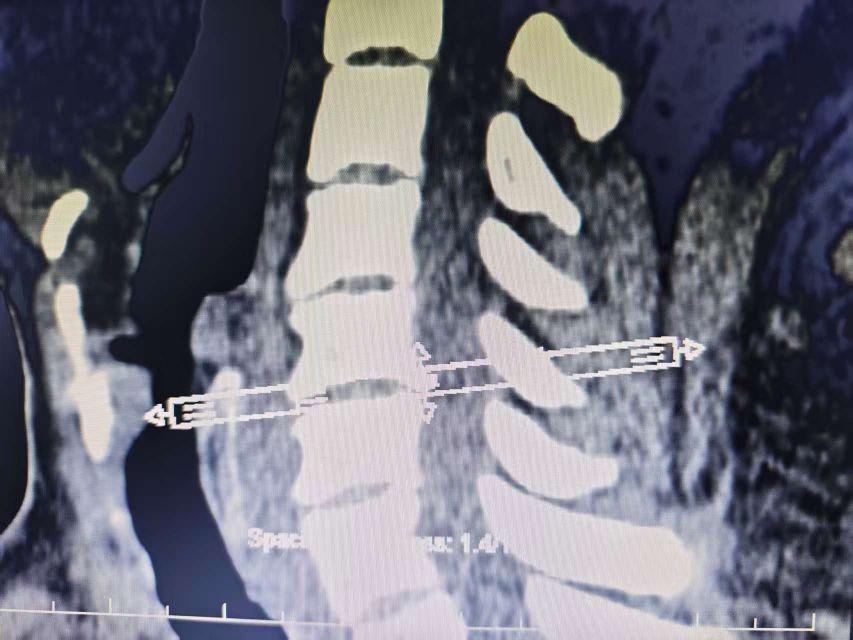

脊柱與骨骺:椎體的生長(zhǎng)板同樣受累,表現(xiàn)為終板不規(guī)則、椎間隙輕度狹窄(但無(wú)強(qiáng)直性脊柱炎的骨橋形成),而腕、膝、髖等負(fù)重關(guān)節(jié)則因軟骨磨損加速,出現(xiàn)早期的關(guān)節(jié)間隙變窄與骨性摩擦。

脊柱同樣受累:腰椎生理前凸減小、胸椎后凸增加,但不同于強(qiáng)直性脊柱炎的“竹節(jié)樣改變”,PPVD的脊柱病變表現(xiàn)為椎體終板不規(guī)則、椎間隙輕度狹窄(X線可見(jiàn)椎體上下緣的“毛刷樣”骨硬化)。此階段患兒常因關(guān)節(jié)疼痛拒絕運(yùn)動(dòng),導(dǎo)致肌肉萎縮與體能下降,進(jìn)一步加重功能障礙。

X線片:早期表現(xiàn)為關(guān)節(jié)周?chē)趋颗虼螅ㄈ缦リP(guān)節(jié)的股骨髁或脛骨平臺(tái)邊緣“波浪狀”增生)、干骺端增寬(生長(zhǎng)板軟骨異常堆積);進(jìn)展期可見(jiàn)關(guān)節(jié)間隙輕度變窄(非炎癥性磨損)、軟骨下骨硬化(類(lèi)似骨關(guān)節(jié)炎,但無(wú)囊性變或骨贅的“邊緣銳利”特征);脊柱表現(xiàn)為椎體終板不規(guī)則、椎間隙均勻狹窄(無(wú)強(qiáng)直性脊柱炎的骨橋或韌帶骨化)。